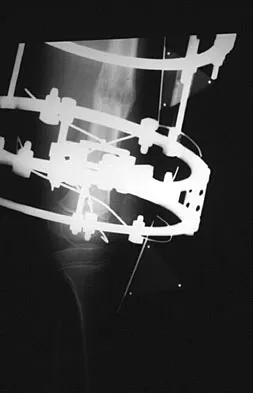

A teenager is undergoing a correction of deformity and lengthening of the femur. Distractions are proceeding as expected; however, during his 6-week follow-up examination, the patient reports that the distraction motors have become harder to turn over for the past 2 to 3 days. Figures 37a and 37b show current radiographs. What is the most likely complication being encountered?